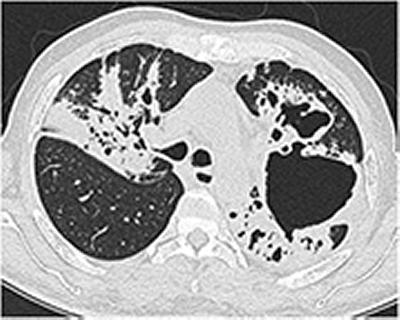

Tuberculosis is a bacterial infection spread through inhaling tiny droplets generated from the coughing of an infected person. It primarily affects the lungs and spreads from person to person by causing cavities within lung tissue. It is a serious condition but can be cured with proper treatment. In 2012, it claimed 1.3 million lives, the vast majority of them in low- and middle-income countries.

Patients with lung cavities are at much greater risk of developing drug-resistance disease, which is a worsening global phenomenon and has resulted in the emergence of untreatable totally drug-resistant strains.